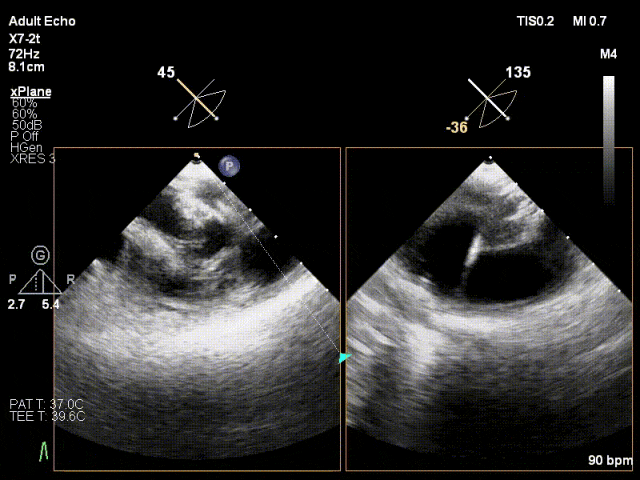

患者为41岁男性,心脏彩超提示:二尖瓣P2脱垂合并房性机制,左心扩大、瓣环扩张,反流主要来源于2区。反流宽度:20mm,2区瓣叶长度:2.2/1.3cm,AP径:43mm,瓣口面积:6.0cm²。

对应策略

X-plane 2区

X-plane 2区彩色